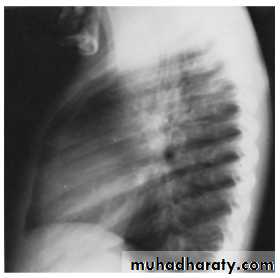

Investigations

In infantile type ECG and CXR show right ventricular hypertrophy with cardiomegaly and pulmonary edema while in older children they show left ventricular hypertrophy and a mildly enlarged heart

In older children(>8 years) the chest x-ray film may show notching

of the ribs due to the development of collaterals.